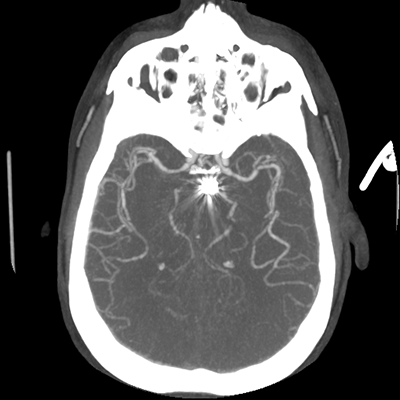

The patient goes down to CT. The following images are obtained. The subdural fluid collection is stable, as is the ventricular caliber.

Starting with the non-contrast head CT, we can appreciate that there's actually not much residual subarachnoid blood at all; it's essentially all resorbed already (and cleared through the EVD). The ventricular caliber is stable. With the CTA head (for convenience's sake, the MIPs were shown), it's subtle, but we can see that the PCAs on each side are not as smooth and regular. The right MCA, starting at the bifurcation, also becomes narrower. This is [radiographic] vasospasm. Now, looking at the CT perfusion-- specifically, the Tmax (MTT) map that were selected-- there's clearly some abnormality within the bilateral cerebellar hemispheres and occipital lobes. Not a lot, but it's there. Delving further into this map, we can appreciate that the areas of abnormality are mainly green, signifying that these areas have Tmax > 6 seconds. This is the threshold that is specific, not sensitive, for vasospasm.

Putting this all together, we have thus identified radiographic vasospasm with the vessel imaging, with perfusion abnormalities that are concordant with it. Does the area of vasospasm and hypoperfusion correlate with the patient's clinical exam?

Yes! It does. The patient had a decline in level of consciousness with diffuse loss of motor function. This does correlate to the basilar territory. (Alternatively, bilateral MCA vasospasm could also be responsible, reminding us that a decline in consciousness could technically be focal/multifocal.) Thus, we can say that this patient does have clinical vasospasm. Whether this will develop into irreversible DCI remains to be seen; at least, the non-contrast head CT and the other portions of the CT perfusion (not shown) currently don't [yet] suggest infarction.